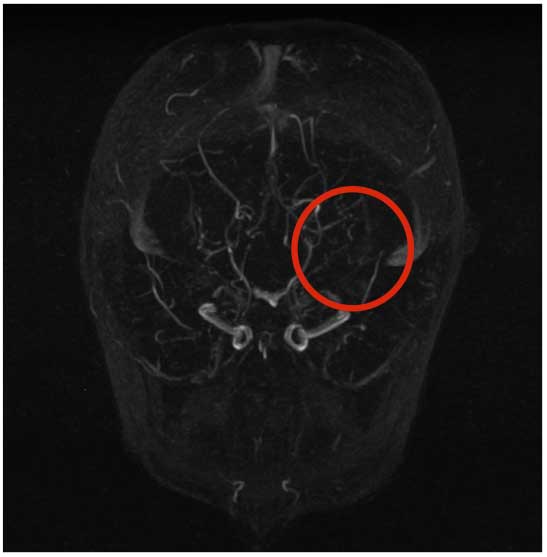

L�ecocardio � risultato nella norma escludendo un�embolizzazione, mentre la normalit� del dosaggio dell�acido lattico nel liquor rendeva improbabile l�ipotesi di una malattia mitocondriale. Anche la ricerca dei virus neurotropi su liquor � risultata negativa. A questo punto l�ipotesi pi� probabile era quella dell�anomalia vascolare: l�angioTC ha evidenziato una riduzione di calibro delle comunicanti anteriori, dell�origine delle arterie cerebrali media e anteriori con circoli collaterali ben visibili (Figura 2).

Figura 2. AngioRMN